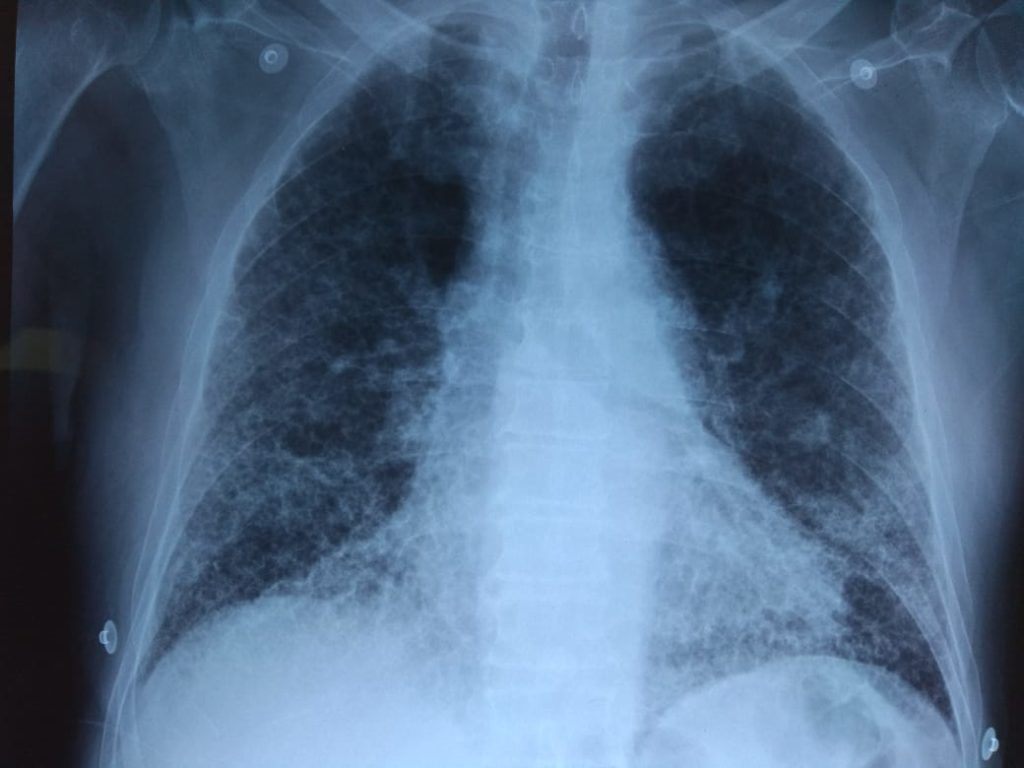

Un grupo de investigación del Consejo Superior de Investigaciones Científicas (CSIC) ha identificado una molécula que actúa sobre el sistema nervioso (un neuropéptido), la cortistatina, como potencial biomarcador para el diagnóstico y tratamiento de enfermedades asociadas a la fibrosis pulmonar, como el daño pulmonar agudo y su forma más severa, el síndrome de dificultad respiratoria aguda.

El estudio, publicado en la revista 'British Journal of Pharmacology', ha demostrado en modelos experimentales preclínicos que la falta de cortistatina provoca una respuesta descontrolada y nociva del sistema inmunitario (la tormenta de citoquinas) y el posterior desarrollo de la reacción fibrótica pulmonar.

Por contra, el tratamiento con cortistatina protege frente a las formas graves de daño pulmonar agudo y el síndrome de dificultad respiratoria aguda. Esta característica la convierte en un candidato para tratar la fibrosis más grave causada por la COVID-19.

Se estima que la fibrosis crónica es la responsable de un tercio de las muertes que se producen en los países desarrollados. Afecta a los órganos vitales y es la causa subyacente de enfermedades con un gran impacto sanitario, como la fibrosis pulmonar idiopática, varios tipos de cirrosis hepática y cardiomiopatías, fibrosis renal o la esclerosis sistémica. Existen evidencias que indican que los enfermos con COVID-19 tienen peor pronóstico cuando la infección viral cursa con fibrosis pulmonar.